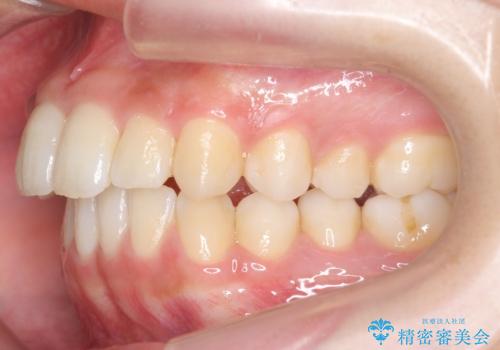

- 出っ歯を主訴に来院。

上の歯を全体に大きく後ろに下げる治療計画を立てました。

後ろに下げるために、親知らずは抜歯しています。